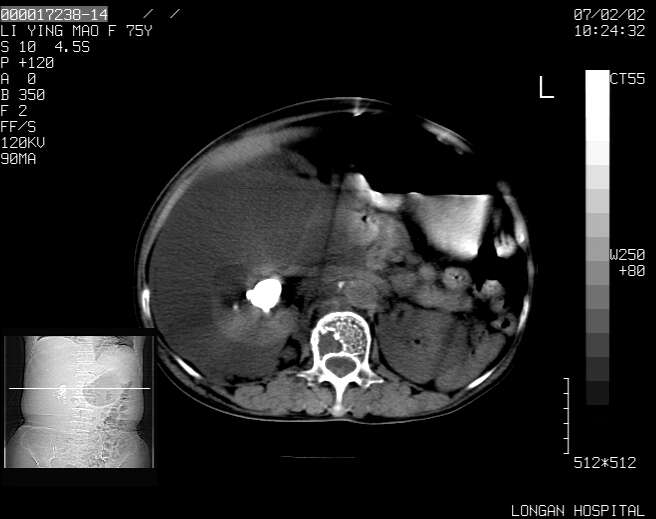

以下是引用dyqct在2007-2-10 8:53:00的发言:[br]考虑:1、肝脏多发囊肿[br] 2、左肾囊肿,右肾多发结石并积水。[br] 3、右胸少量积液。[br] 4、右肾周包裹性积液或淋巴管瘤(有见缝就钻的征象、薄隔、小结节状钙化)?[br] 5、腰椎动脉瘤样骨囊肿?[br] [br] [br]